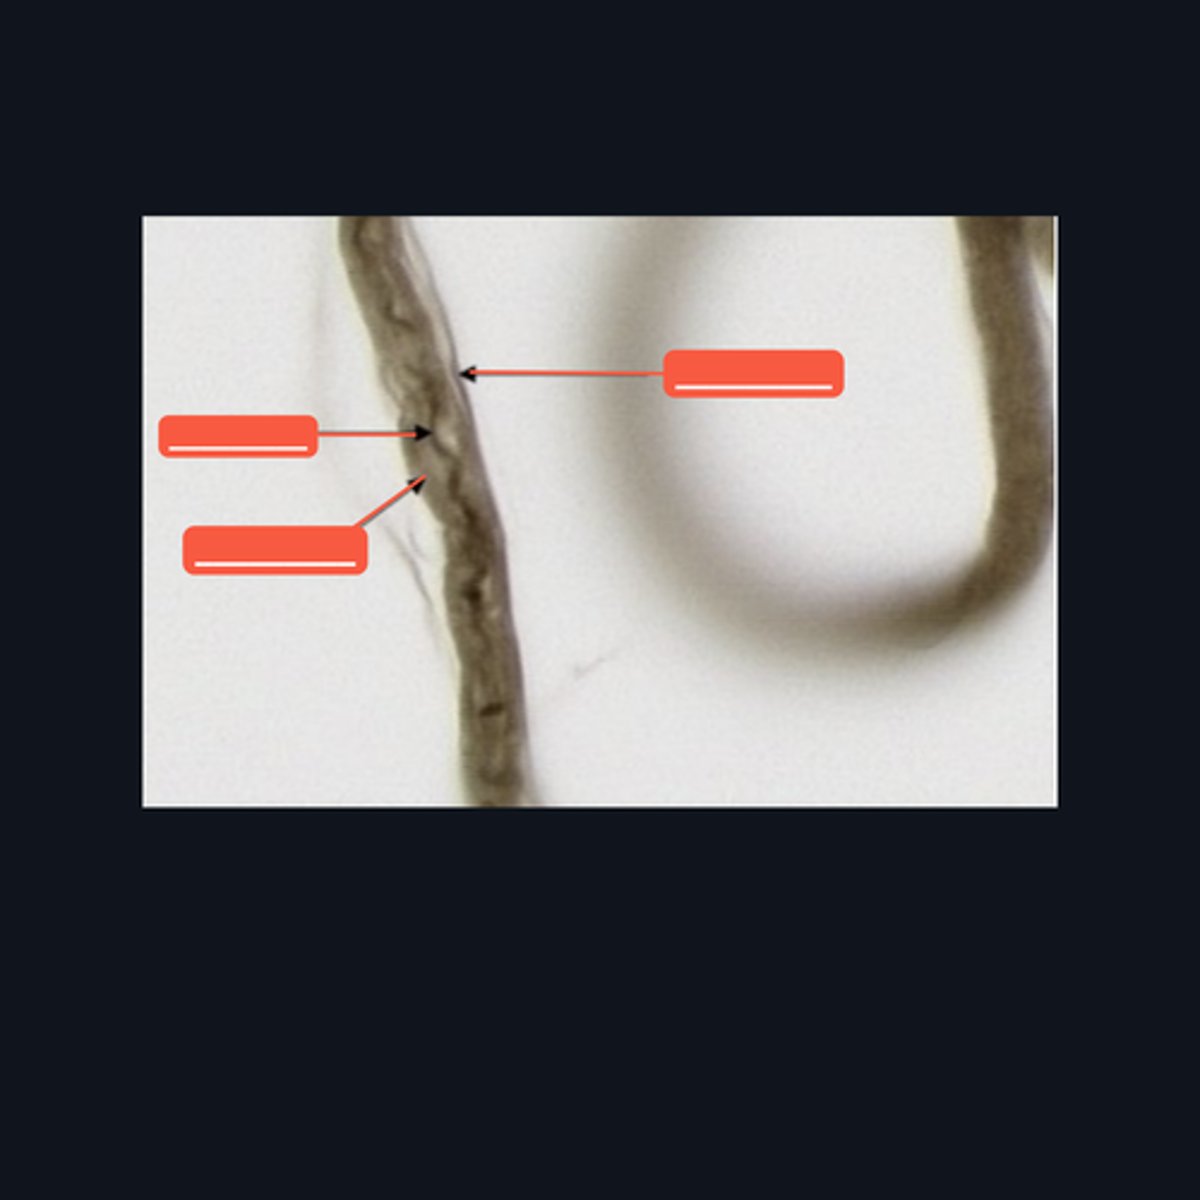

Peripheral Nerve

Identify where this structure is found

(top 3) from left to right

Perineurium

Axon

Myelin sheath

(bottom 2) from left to right

Endoneurium

Schwann cell

Identify the pointed structures.

Peripheral Nerve

Identify the structure on the image.

(top to bottom)

Axon

Endoneurium

Myelin sheath

Identify the pointed structures.